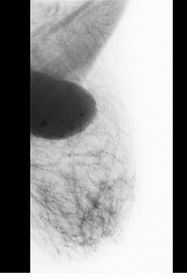

Na MG

snímcích (obr. 1) je v obou projekcích sin

vidět kulovité, neostře ohraničené, nehomogenní ložiskové zastínění

bez mikrokalcifikací vel. asi 3x2 cm.